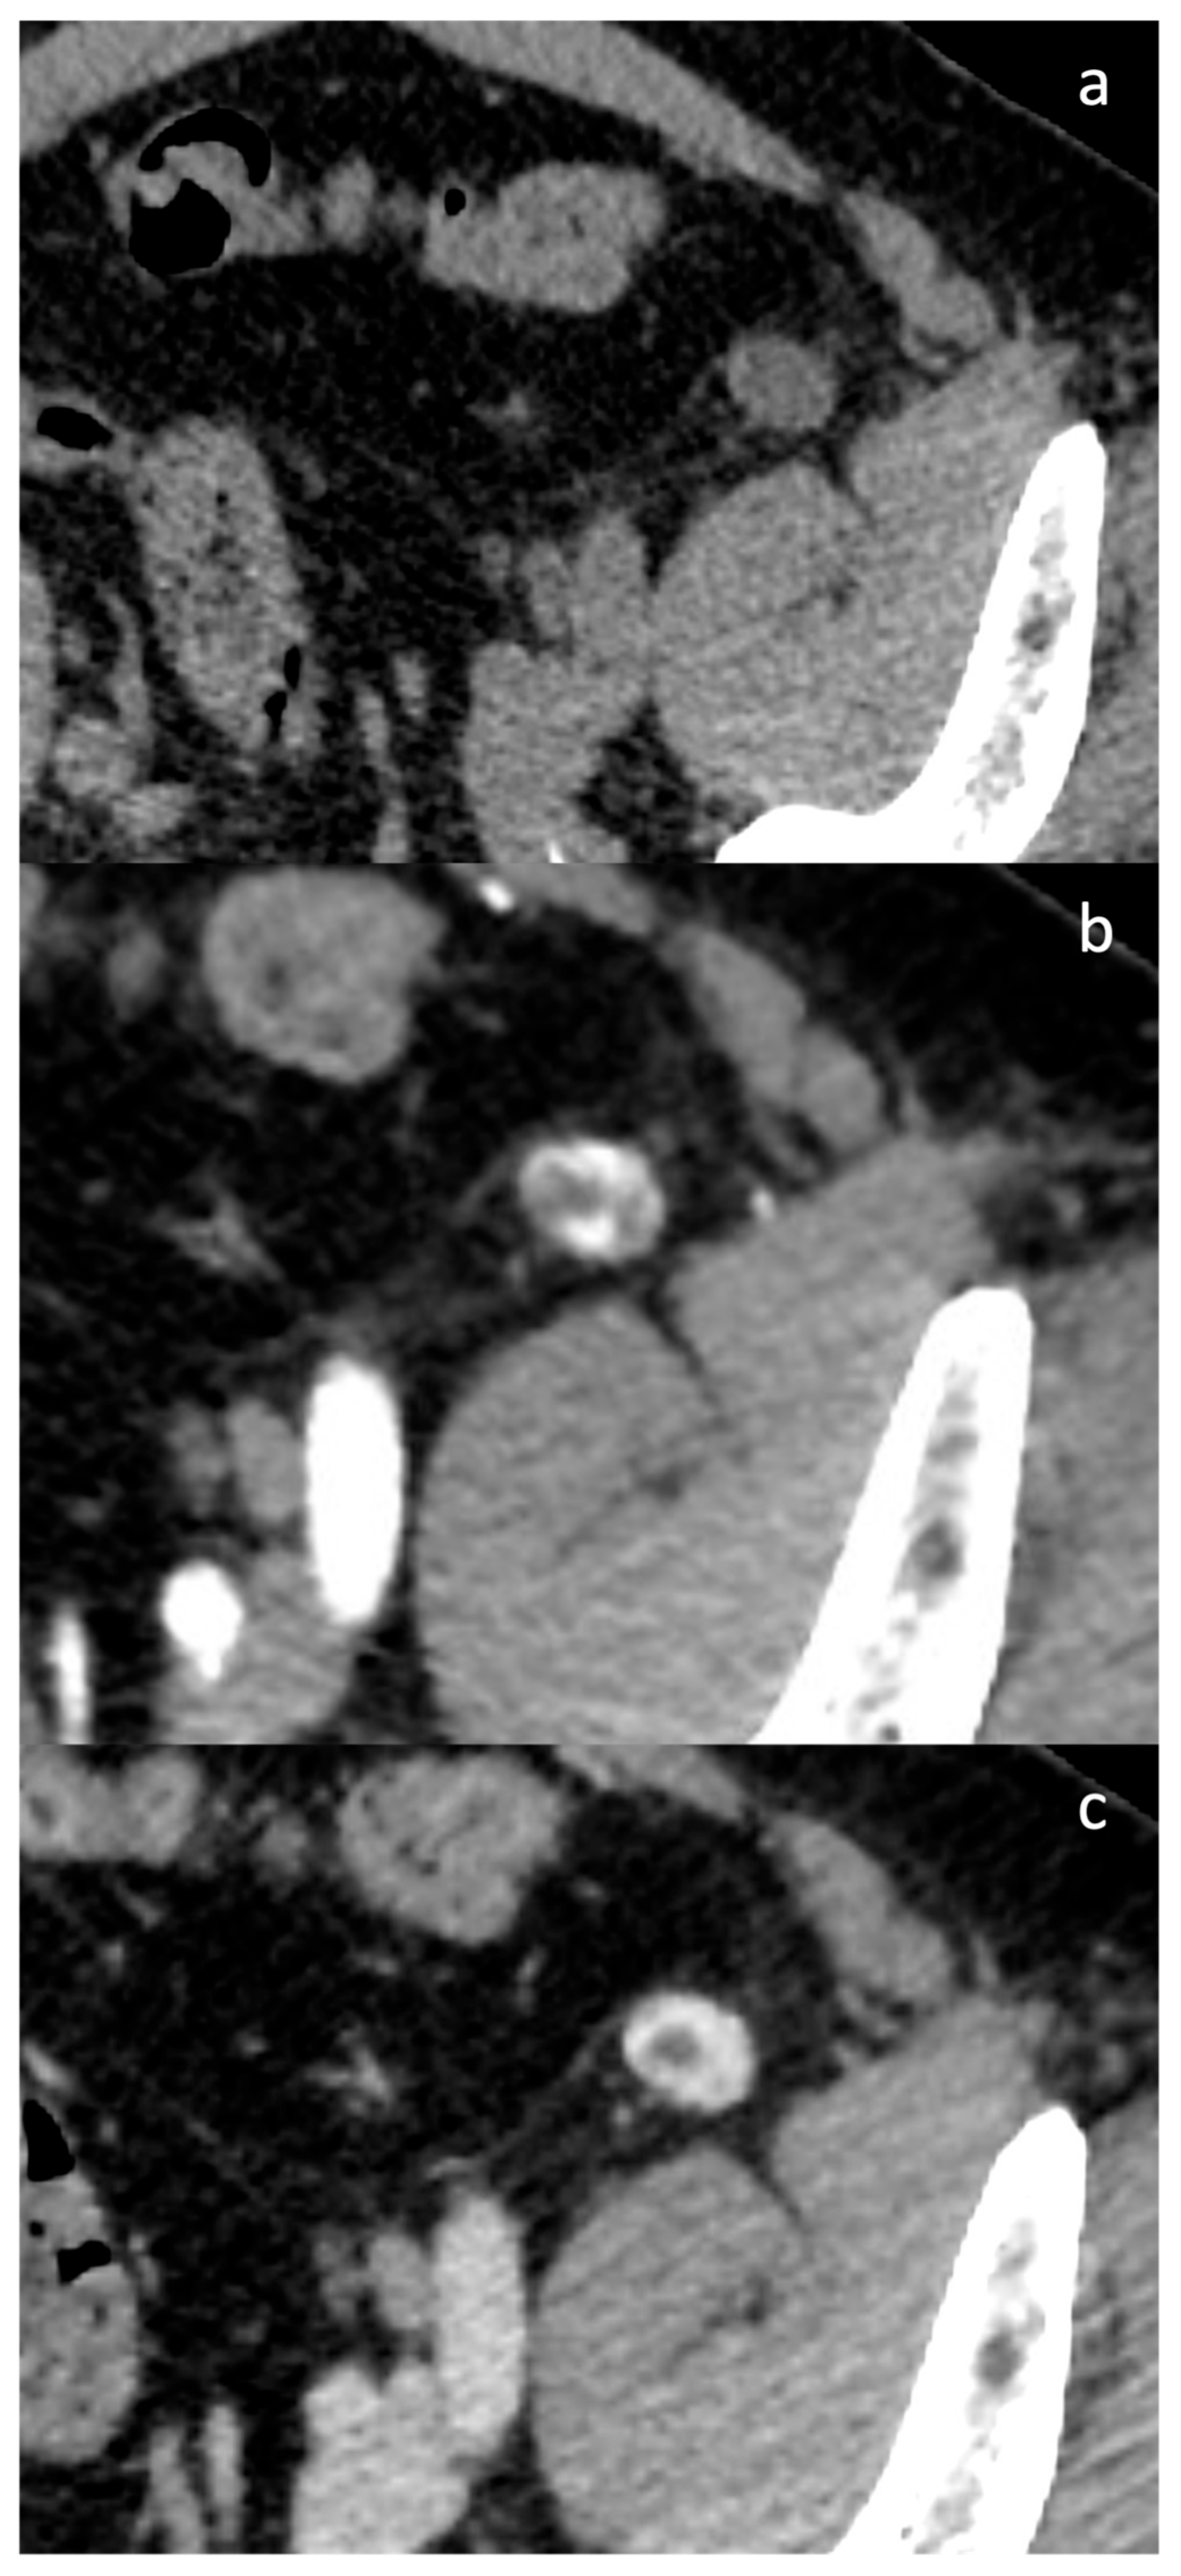

3.2. Case Presentation

4.3. Diagnostic Challenges and Imaging Limitations

- A solid homogeneous well circumscribed lesion, without calcifications, with a characteristic CT and MRI contrast enhancement, as described in many case reports in the literature;